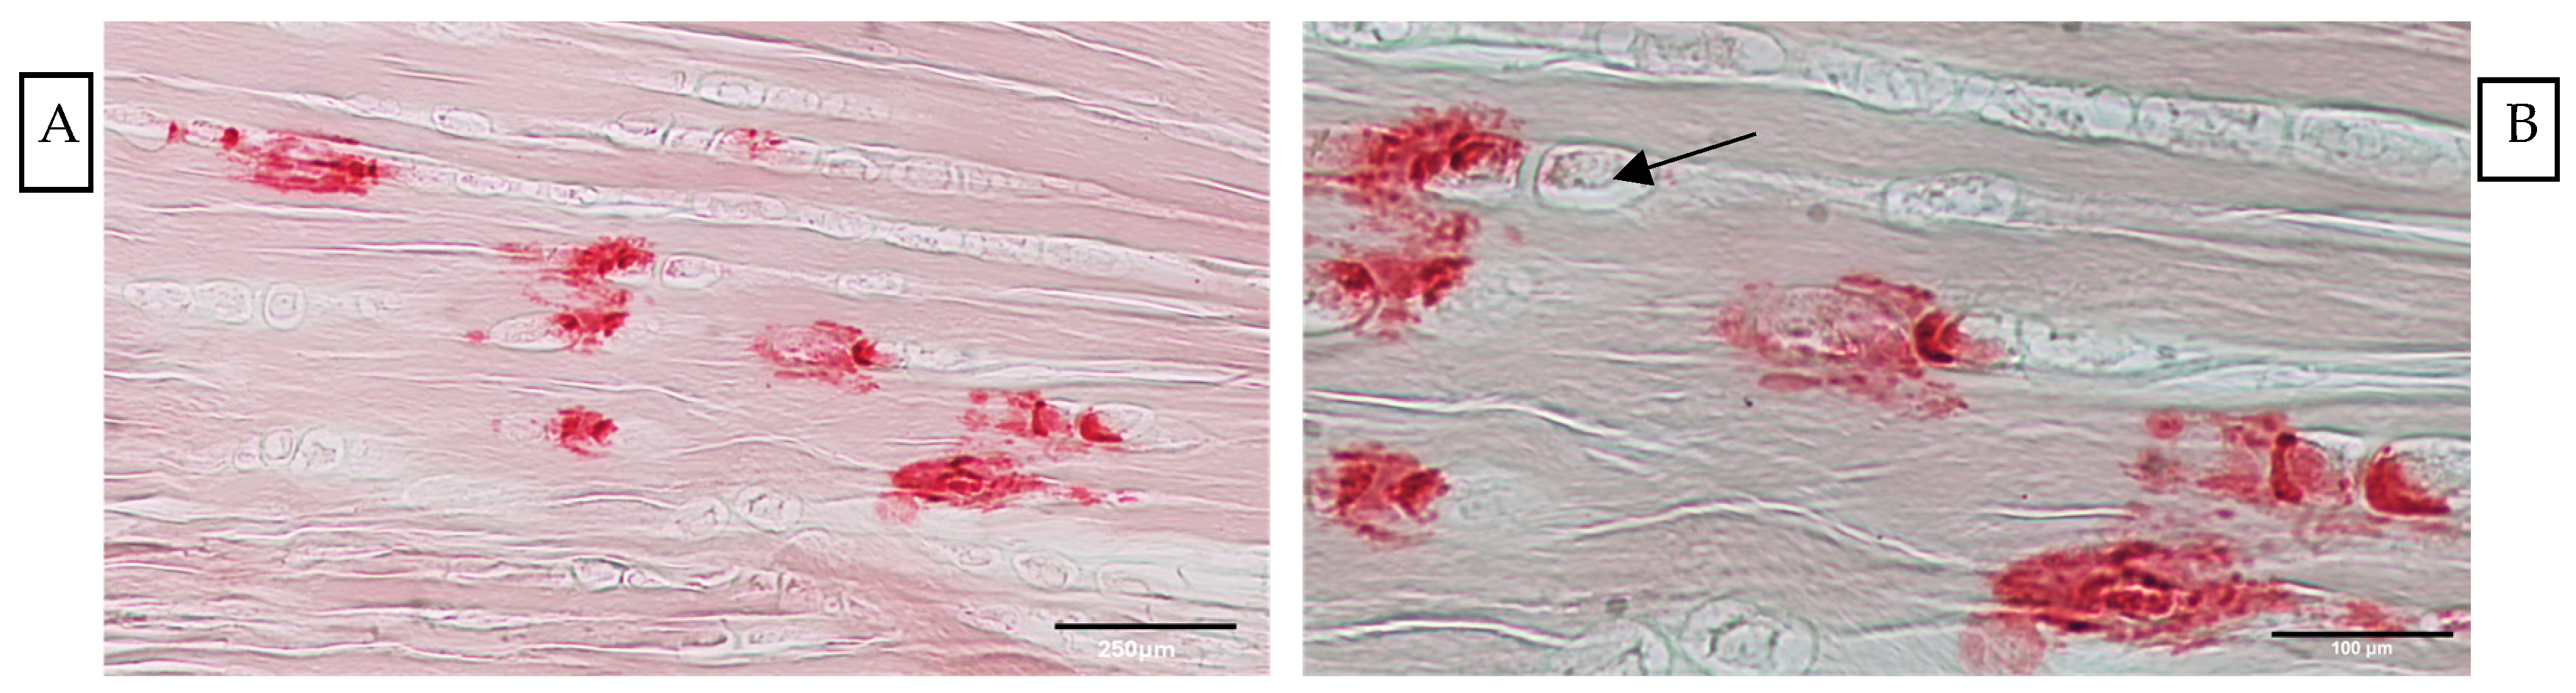

- Alizarin Red, used to detect the presence of calcium deposits in the tissue [27].